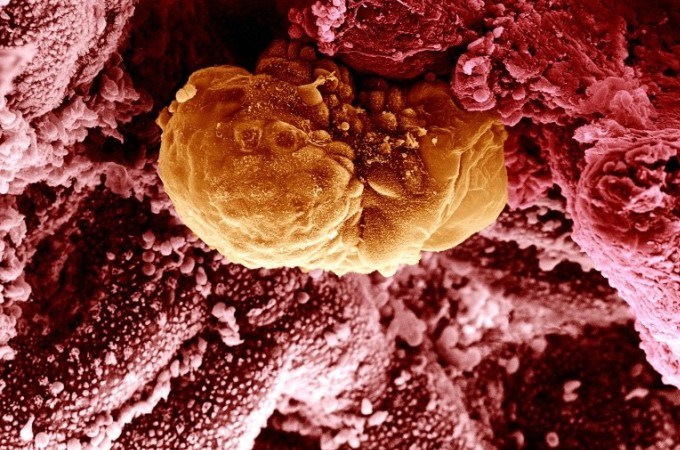

Медицина и диагностика: Инвазивный пузырный занос на УЗИ